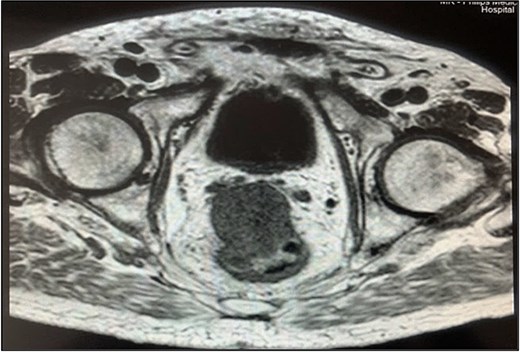

Pelvic magnetic resonance imaging (MRI) revealed a extrarectal lesion located 8 cm from the anal verge, with 4 × 4 cm, suspicious of tumoral deposit in the mesorectum (Figs 5 and 6).

Rectal endoscopic ultrasound revealed an extrinsic lesion on the rectal wall, within the mesorectum (Fig. 4). The biopsy was suggestive of adenocarcinoma.